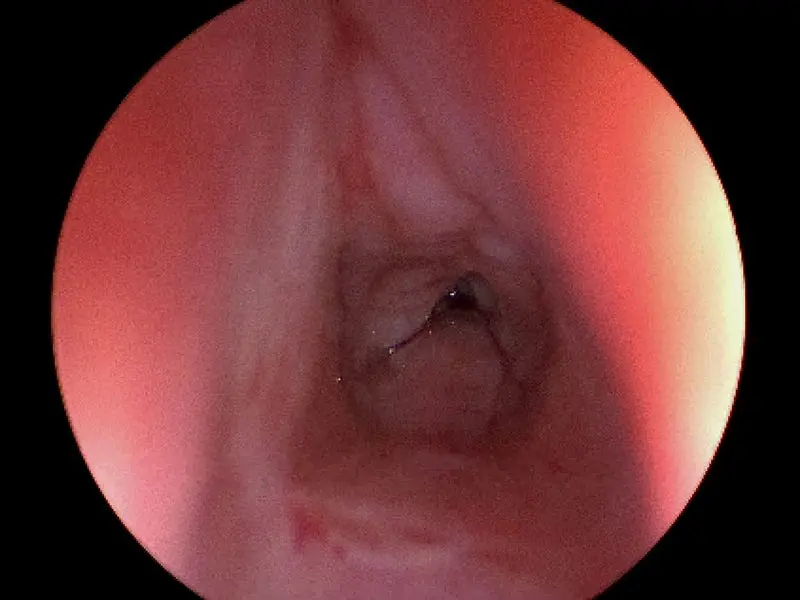

A patient that was previously intubated for COVID-19 who has developed posterior glottic stenosis.